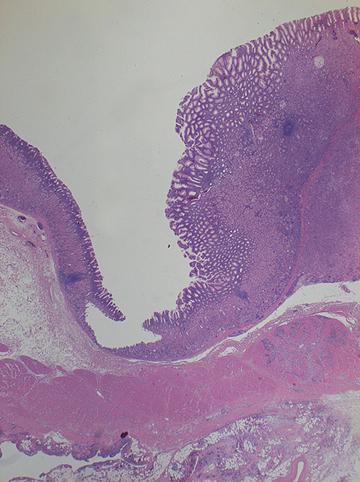

疾病(病理主体)的分类恶性上皮性肿瘤/腺癌

部位(按器官分)胃(部位)/2个以上

检查方法病理切片(微观)

肿瘤的肉眼分类4型(弥漫浸润型)/

肿瘤最大直径40以上

肿瘤的深度s(a)